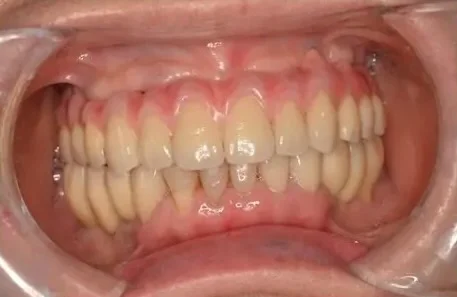

Before

After

上下左右側における歯が多数なくなったところへのインプラント治療(虫歯・歯周病における多数歯欠損)

1年、20回 / 7,700,000円リスク・副作用:多数歯インプラントケースとなり、治療期間の長期化およびインプラント周囲炎のリスク